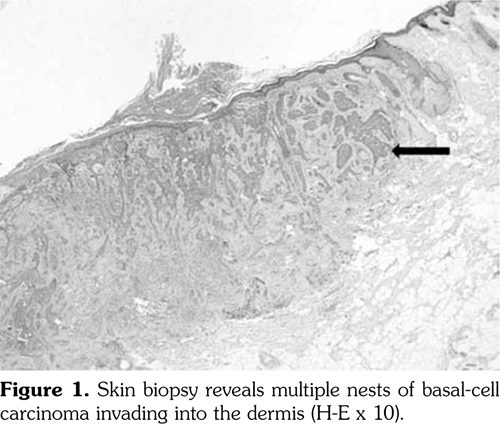

Two years later, the patient presented with an ulcer on the left nasolabial groove. Skin biopsy of the affected tissue revealed damaged epidermis with basal-cell carcinoma infiltration in the dermis (Figure 1), suggesting basal-cell carcinoma for which she underwent a resection. There were no clinical or laboratory signs suggestive of DM activity.